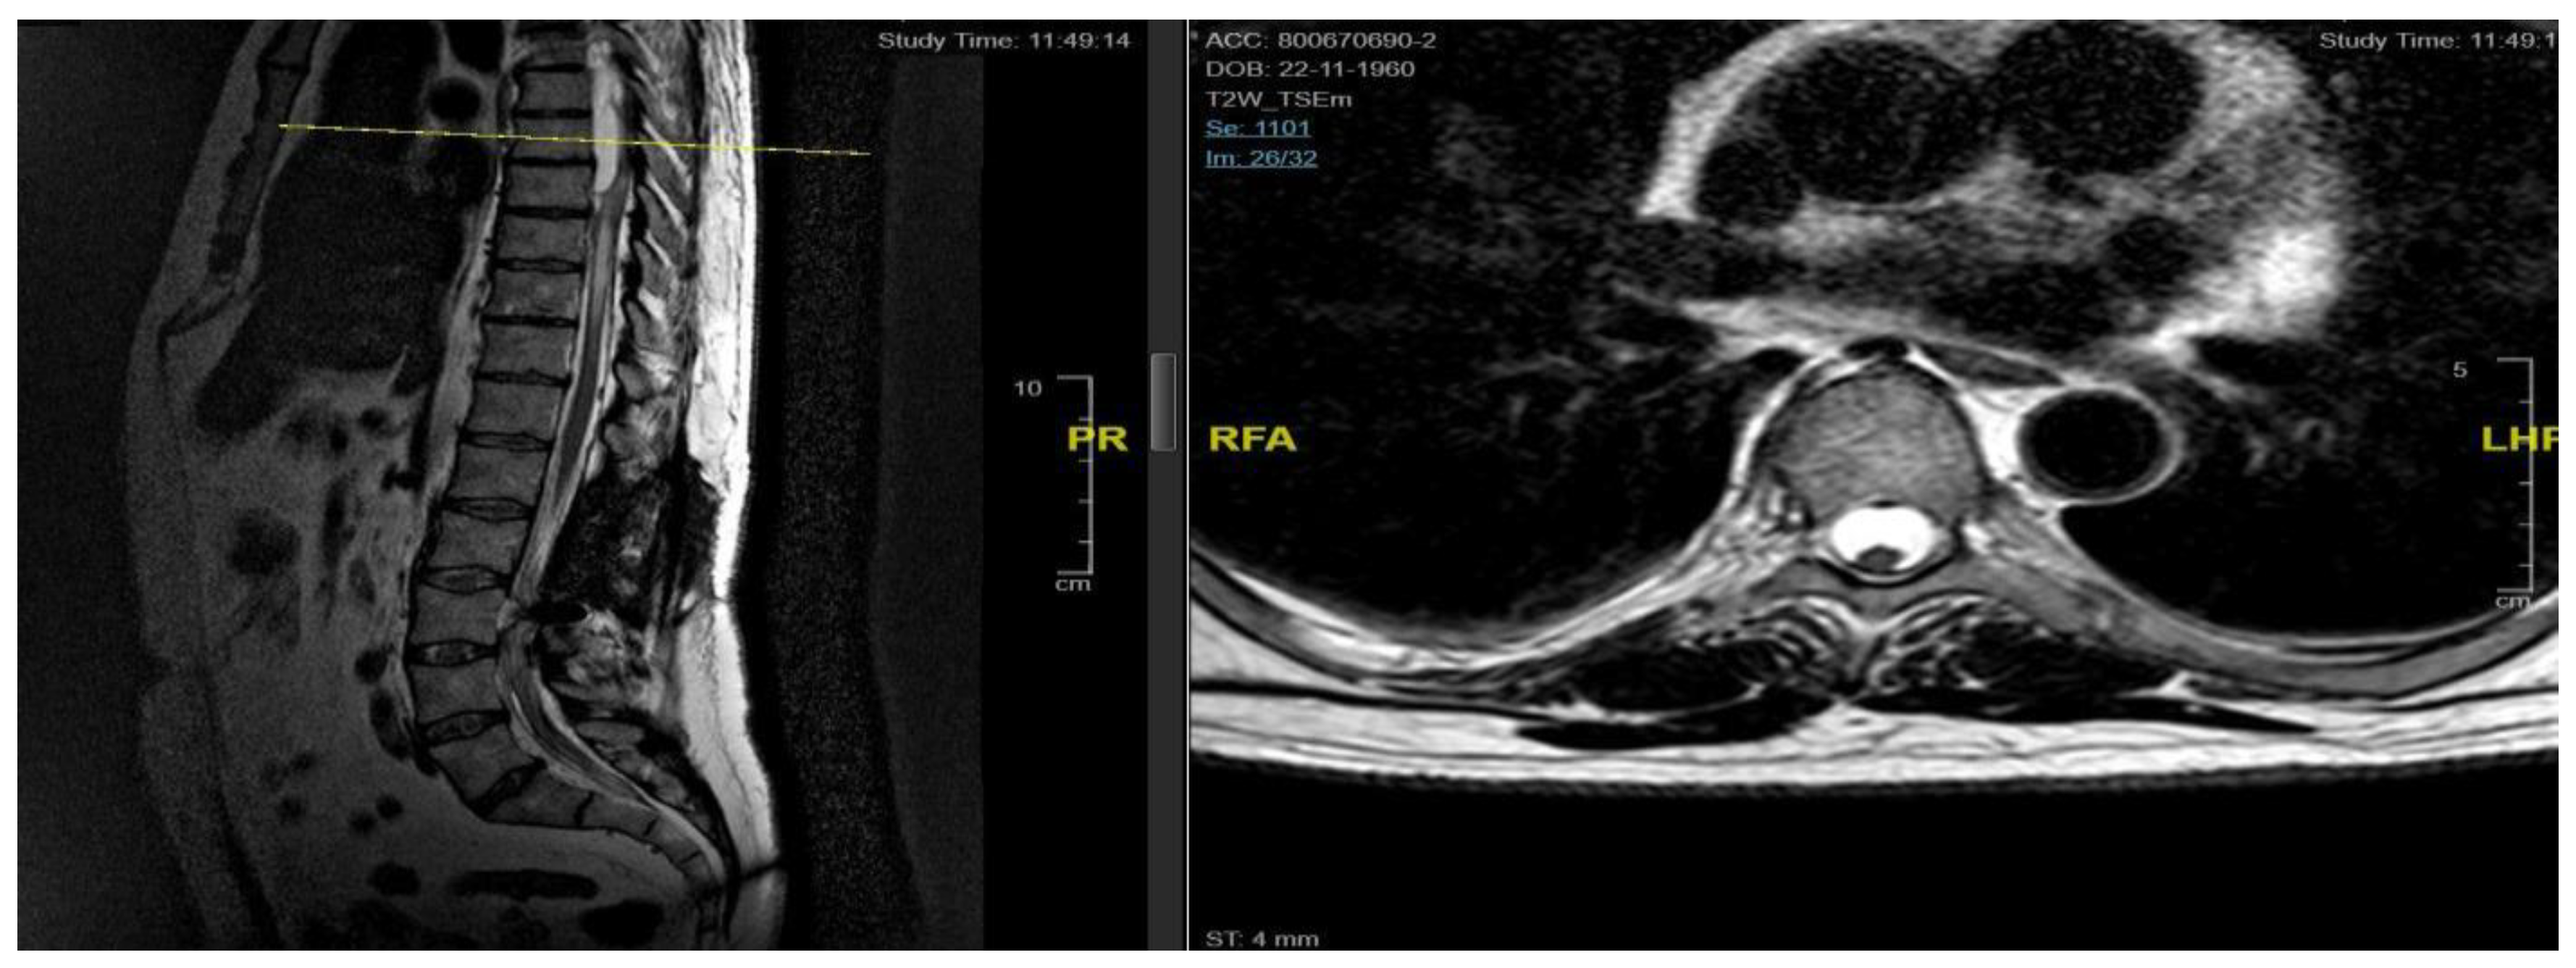

A 46-year-old man with a history of post traumatic burst fracture of L1 in a car accident, treated with lumbar fusion at D12-L2, developed seven months later lower limb weakness, sensory loss, and bladder and bowel dysfunction [Figure 1]. MRI revealed syringomyelia at D12-L2 compressing the conus medullaris. Initial surgery involved syrinx decompression through myelotomy, leading to significant symptom improvement. However, three months later, his symptoms recurred with an increased syrinx size. A second surgery introduced a syringo-subarachnoid shunt and removed scar adhesions, with temporary improvement although a post operative cerebrospinal fluid fistula occured. He underwent a third surgery with a syringo-peritoneal shunt, resolving the syrinx. Post-operatively, a follow-up MRI showed a significant reduction in the syrinx size and improvement in myelopathy: the patient’s neurological status improved, with gradual recovery of bladder and bowel functions.

Figure 1. Case 1: pre-operative MRI (left) and post-operative MRI (right).